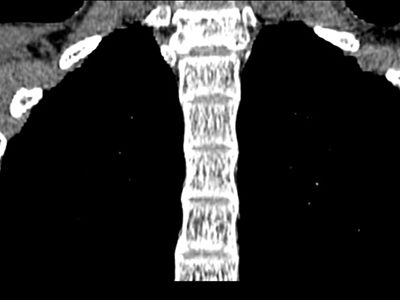

CTCe este investigația CT Ghidul Pacientului CT Servicii și Preţuri CT Echipa medicala radiologie CT Dotare CT Examinări CT CT cerebral CT coloană vertebrală CT torace CT abdomen CT pelvis CT membre CT articulaţii Angiografia CT Uro CT Perfuzie CT Hidro-colono CT coloană vertebrală Aplicații: traumatisme, fracturi, hernii de disc.